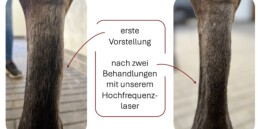

Der 12-jährige Wallach „Valentino“ (Name geändert) lahmt vorberichtlich seit drei Wochen aufgrund eines Schadens am Unterstützungsbands vorne links. Er wurde uns erneut mit deutlicher Schwellung an der benannnten Stellte vorgestellt. Wir stuften die Lahmheit als eine 4/5 ein.

Wir therapierten Valentino mit Boxenruhe, entzündungshemmenden Medikamenten und einer regelmäßigen Lastertherapie.

Verlauf:

- regelmäßige Untersuchung mit unserem hochfrequenten Laser

Fazit:

Fotogalerie